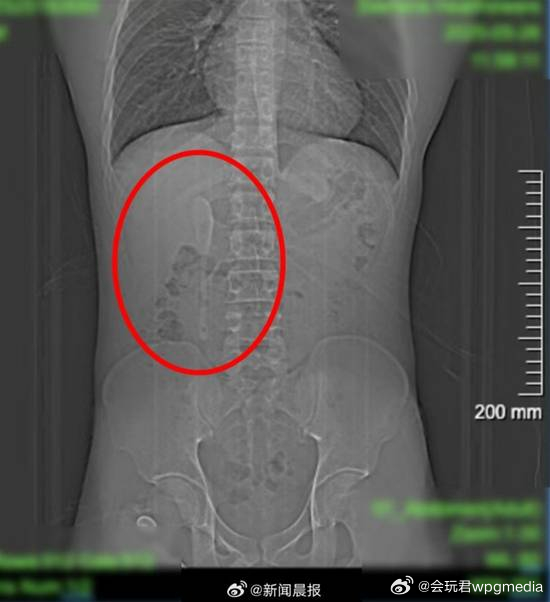

小伙腹痛CT查出肠道卡2把勺子 称吃东西时不慎吞下据荔枝新闻报道,近日,江苏南京,28岁小伙因腹痛就医,CT检查发现肠道内竟卡着2把勺子。患者称是食用新疆食品时不慎吞下,起初以为只有1把,肠镜检查后确认是2把。勺子卡在回肠末端,周围黏膜已形成溃疡,随时有穿孔风险。因异物长约12公分,且位于肠腔狭窄的小肠内,取出难度较大。医生经过近一小时操作,成功将两把勺子完整取出。医生提醒,误吞异物在临床较为常见,可能引发消化道穿孔、出血等严重后果,一旦发生需在 24 小时内及时就医处理,避免出现严重并发症。